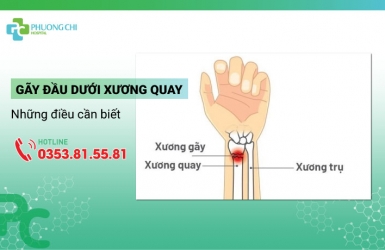

Gãy Đầu Dưới Xương Quay Và Những Điều Cần Biết

Gãy đầu dưới xương quay là một trong các chấn thương xương thường gặp ở vùng cổ tay xuất hiện các vết nứt hoặc bị gãy. Gãy đầu dưới xương quay thường xảy ra do ngã chống tay với bàn tay duỗi quá mức, đây là nguyên nhân hay gặp nhất.